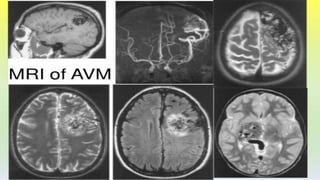

INVESTIGATIONS

Angiography

Magnetic resonance

Transcranial Doppler ultrasound

Diagnostic evaluation

• MRI is the investigation of choice as cavernous

malformations, are often missed on CT scanning

and rarely seen on angiography. Most lesions

show marked signal change around this lesion

due to a rim of hemosiderin deposition.

• Angiography (DSA)- Cavernous malformations

are angiographically occult and do not

demonstrate arteriovenous shunting.